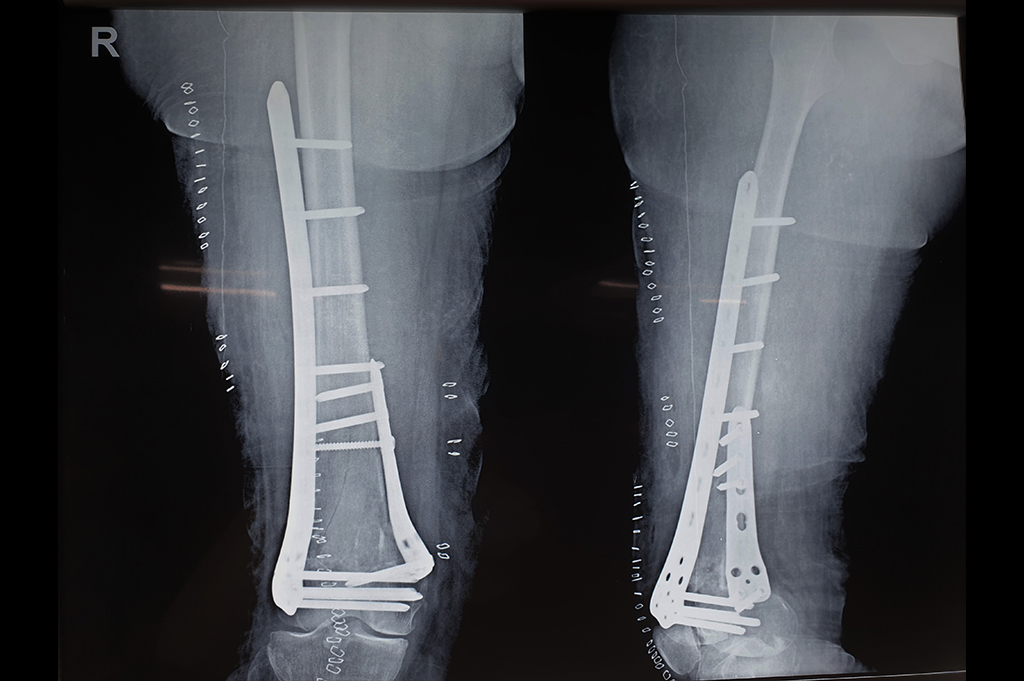

Periprosthetic Fracture THR